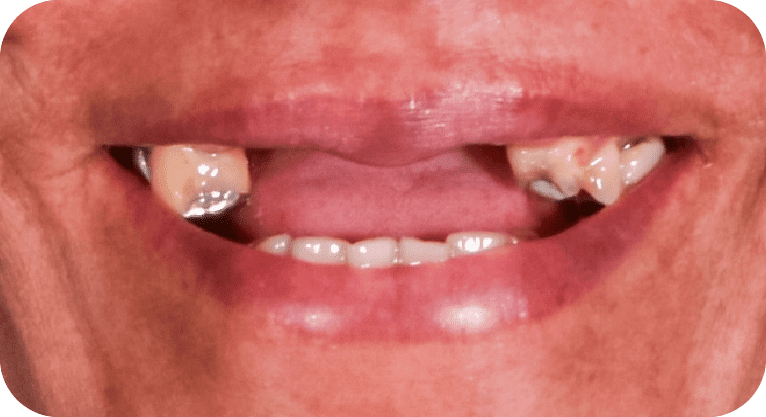

Female patient, “52” years old

Treatment: All-on-4

The patient came to the clinic aer losing several upper teeth due to cavities and was using a removable denture that she founduncomfortable. She wanted a fixed solution, so a full rehabilitation was performed using the All-on-4 technique, placing 4 dental implants that support a fixed prosthesis. This restored her functionality, confidence, and a natural-looking smile permanently.